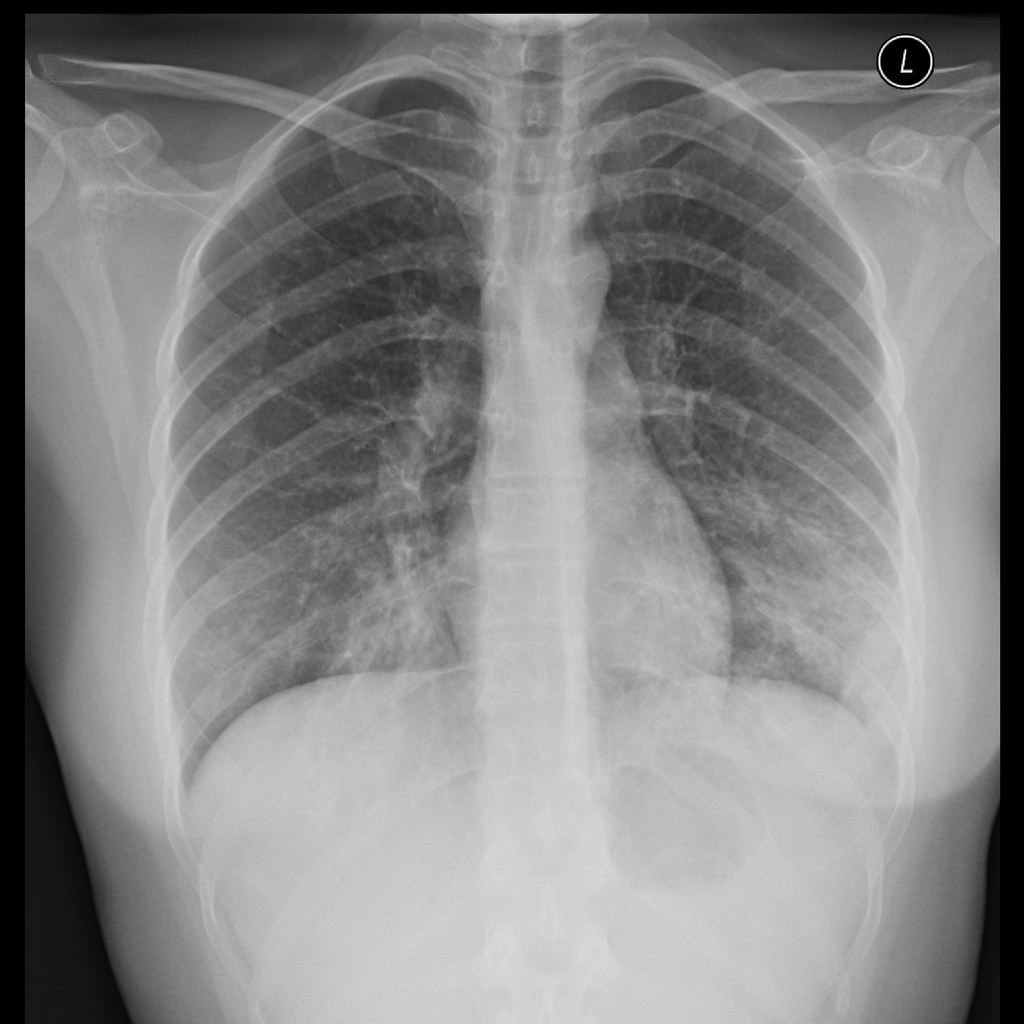

#MicroMonday. A 21 year old college student living in a dorm presents with 1 week of general malaise, cough, pleuritic chest pain, and fevers. He has +sick contact. CXR shows the following:

Likely mycoplasma! This CXR + symptoms are suggestive of an atypical PNA, such as mycoplasma. On CXR you will see reticular nodular opacities or patchy consolidations rather than large or lobar consolidations.